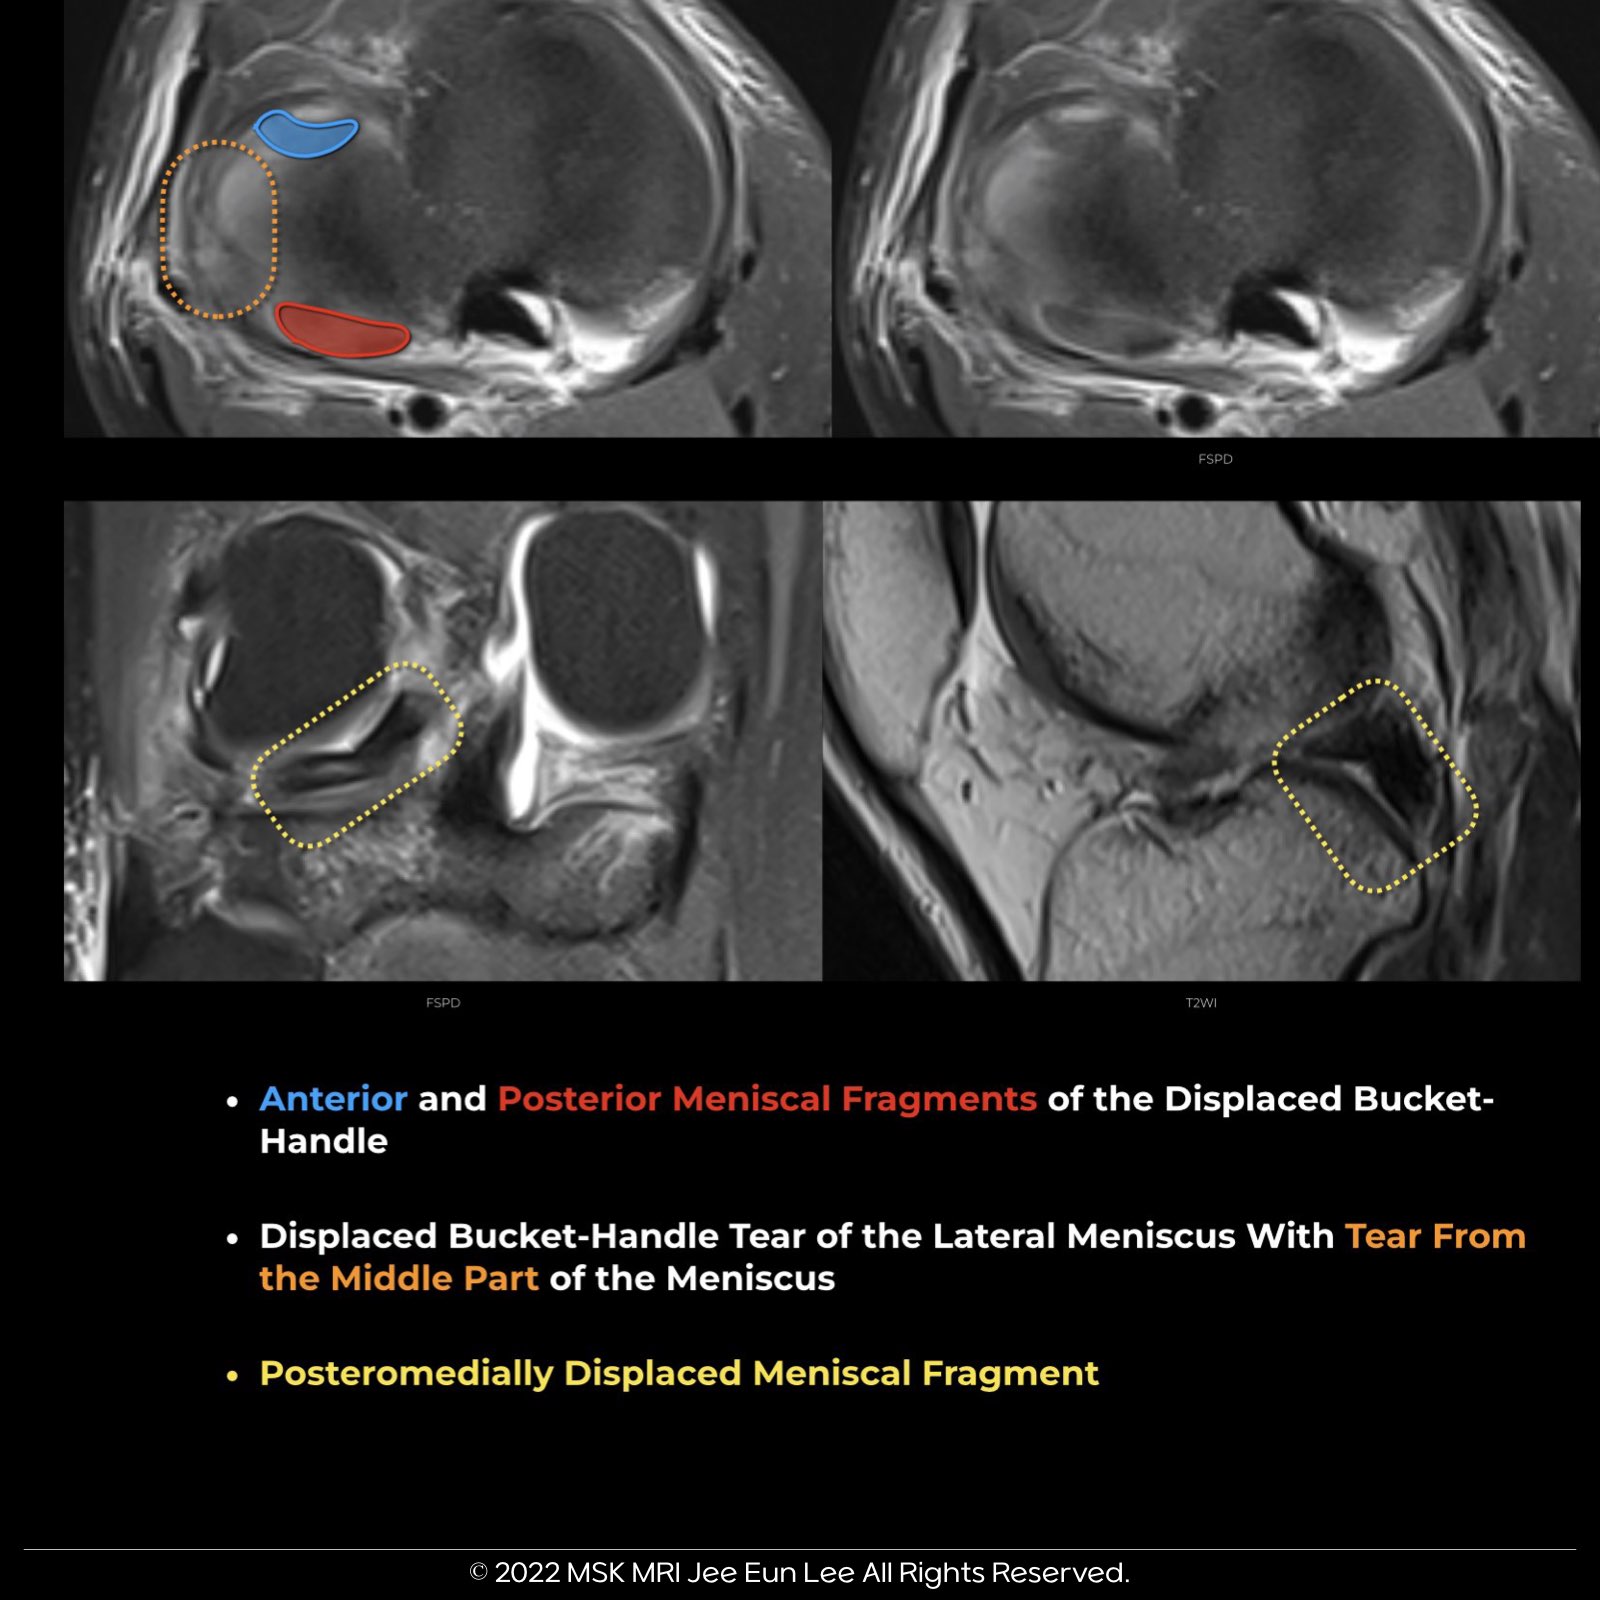

Broken bucket handle meniscal tears

- This entity refers to a bucket handle tear with an additional rupture of the meniscal fragment.

- Broken bucket handle tears are often difficult to identify on MRI.

- However, it is a crucial injury to be aware of and recognize, as the mobility of the ruptured fragments results in significant pain and joint locking.